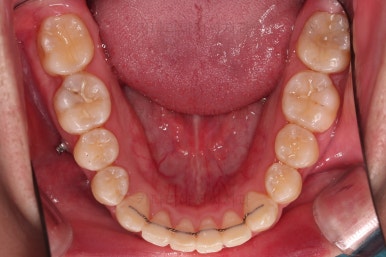

부산교정치과 초진 시 입안의 모습입니다.

앞니가 삐뚤어서 결손치아가 없었더라도 교정치료를 원하셨던 상황이었고요.

오른쪽 어금니 맞물림은 결손치아도 그렇지만 전반적인 앞뒤 차이가 있는 부정교합이 있었어요.